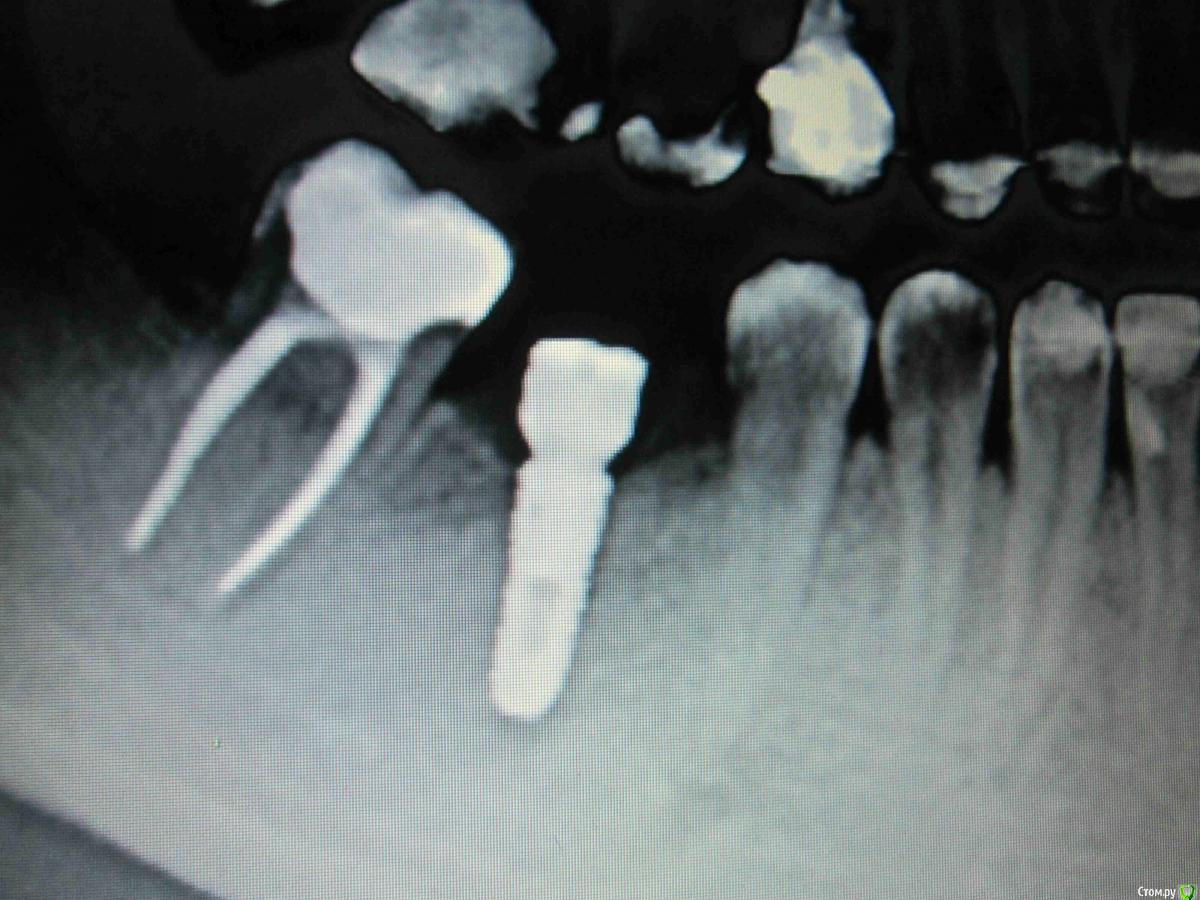

SDC Опубликовано 21 февраля, 2015 Поделиться Опубликовано 21 февраля, 2015 (изменено) Уже. Седьмой зуб наклонился вперед, а верхний пятый опустился вместе с десной - проследите за контуром шеек зубов.Дальше будет как повезет.Дырка формирователя под отвертку не должна интересовать микробов, а Вас - микробы в дырке формирователя )))Да, для лучшей гигиены и эстетики необходимо увеличение объема десны, но лет 4-5 назад о десне вопросов не возникало - это современная опция. Изменено 21 февраля, 2015 пользователем SDC 3 Ссылка на комментарий

SDC Опубликовано 22 февраля, 2015 Поделиться Опубликовано 22 февраля, 2015 (изменено) Хотелось бы просто уточнить, какова вероятность,что имплант такой стоит себе без проблемВ таком случае выкладыйте все снимки для оценки специалистами. И какой то прогноз можно будет дать, но все равно может оказаться не так, как хочется и когда Вы соберетесь протезироваться, может окажется,что кость атрофировалась и нужно все заново делать По прицельному снимку возможно оценить уровень костной ткани в одной плоскости относительно имплантата и на основании этого сделать выводы о "нормально и отлично" Изменено 22 февраля, 2015 пользователем SDC Ссылка на комментарий